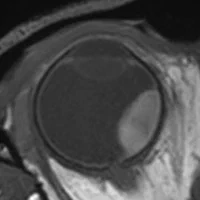

New MRI technologies to improve the care for eye tumor patients.

Through MRI-based radiotherapy planning we aim to preserve more of patients’ vision.